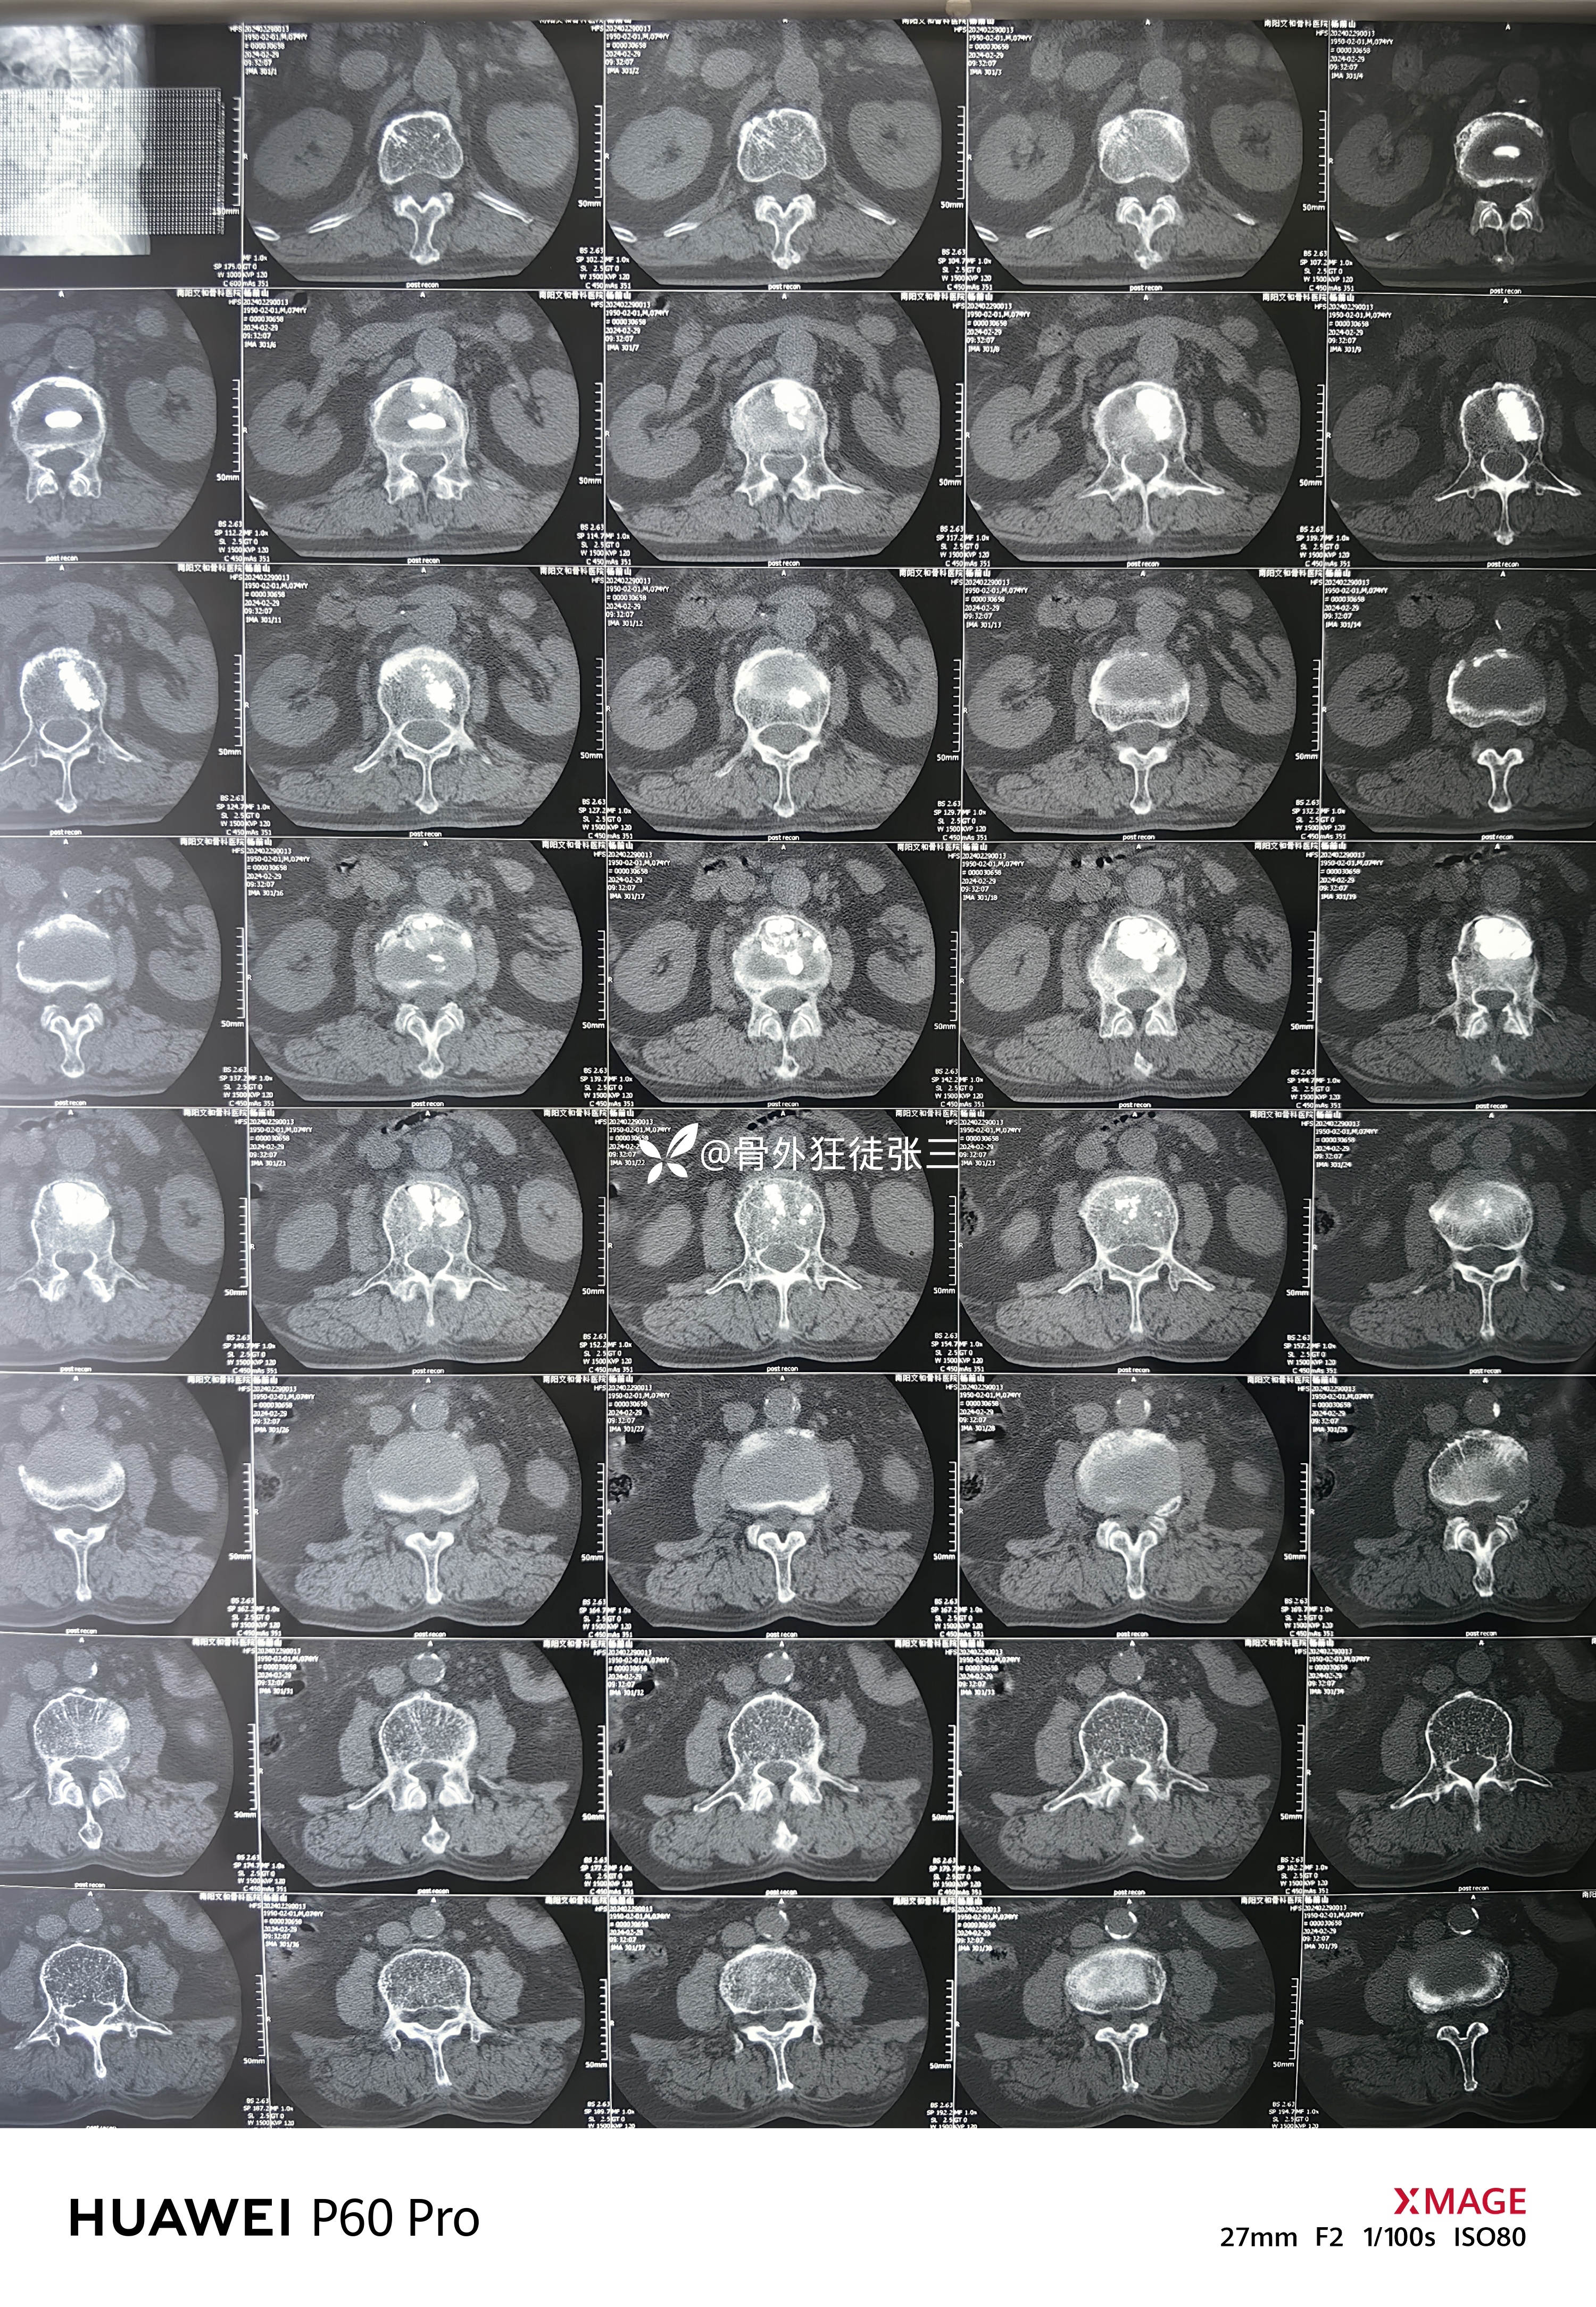

辅助检查:

(因心脏多个支架,核磁未做)

考虑疼痛原因为骨水泥单侧弥散